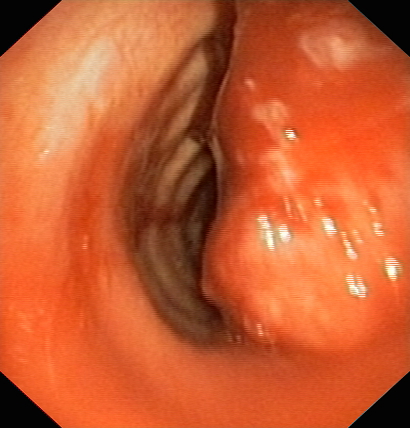

Фибротрахеобронхоскопия: Рак трахеи до и после проведения внутрипросветной брахитерапии с синхронной полихимиотерапией